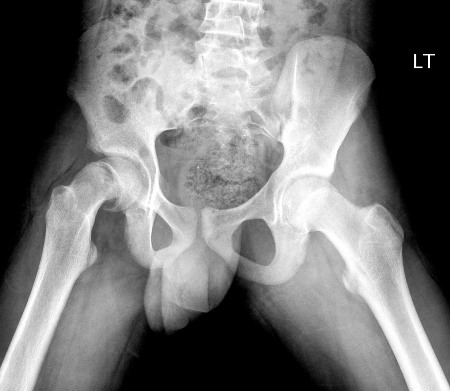

Plain x-rays should be ordered for all patients with suspected SCFE. On the antero-posterior view, Klein's line, which is drawn along the superior aspect of the femoral neck, normally intersects some part of the femoral head in a healthy hip.[Figure caption and citation for the preceding image starts]: Klein lines are drawn along the superior cortex of the femoral neck. A normal Klein line will intersect the epiphysis. An abnormal Klein line does not intersect the epiphysis, as the femoral neck has moved proximally and anteriorly relative to the epiphysisImage courtesy of John M. Flynn, MD [Citation ends].

Other radiographical findings may include widening of the physis on the affected side, loss of the overlap of the metaphysis of the proximal femur (Capener’s sign), or increased sclerosis of the proximal metaphysis on the AP view, where the slipped epiphysis overlies the metaphysis as a double shadow (blanch sign of Steel).[33][34]

Klein's line does not intersect the femoral head; may show widening of physis, loss of Capener’s sign, or positive blanch sign of Steel